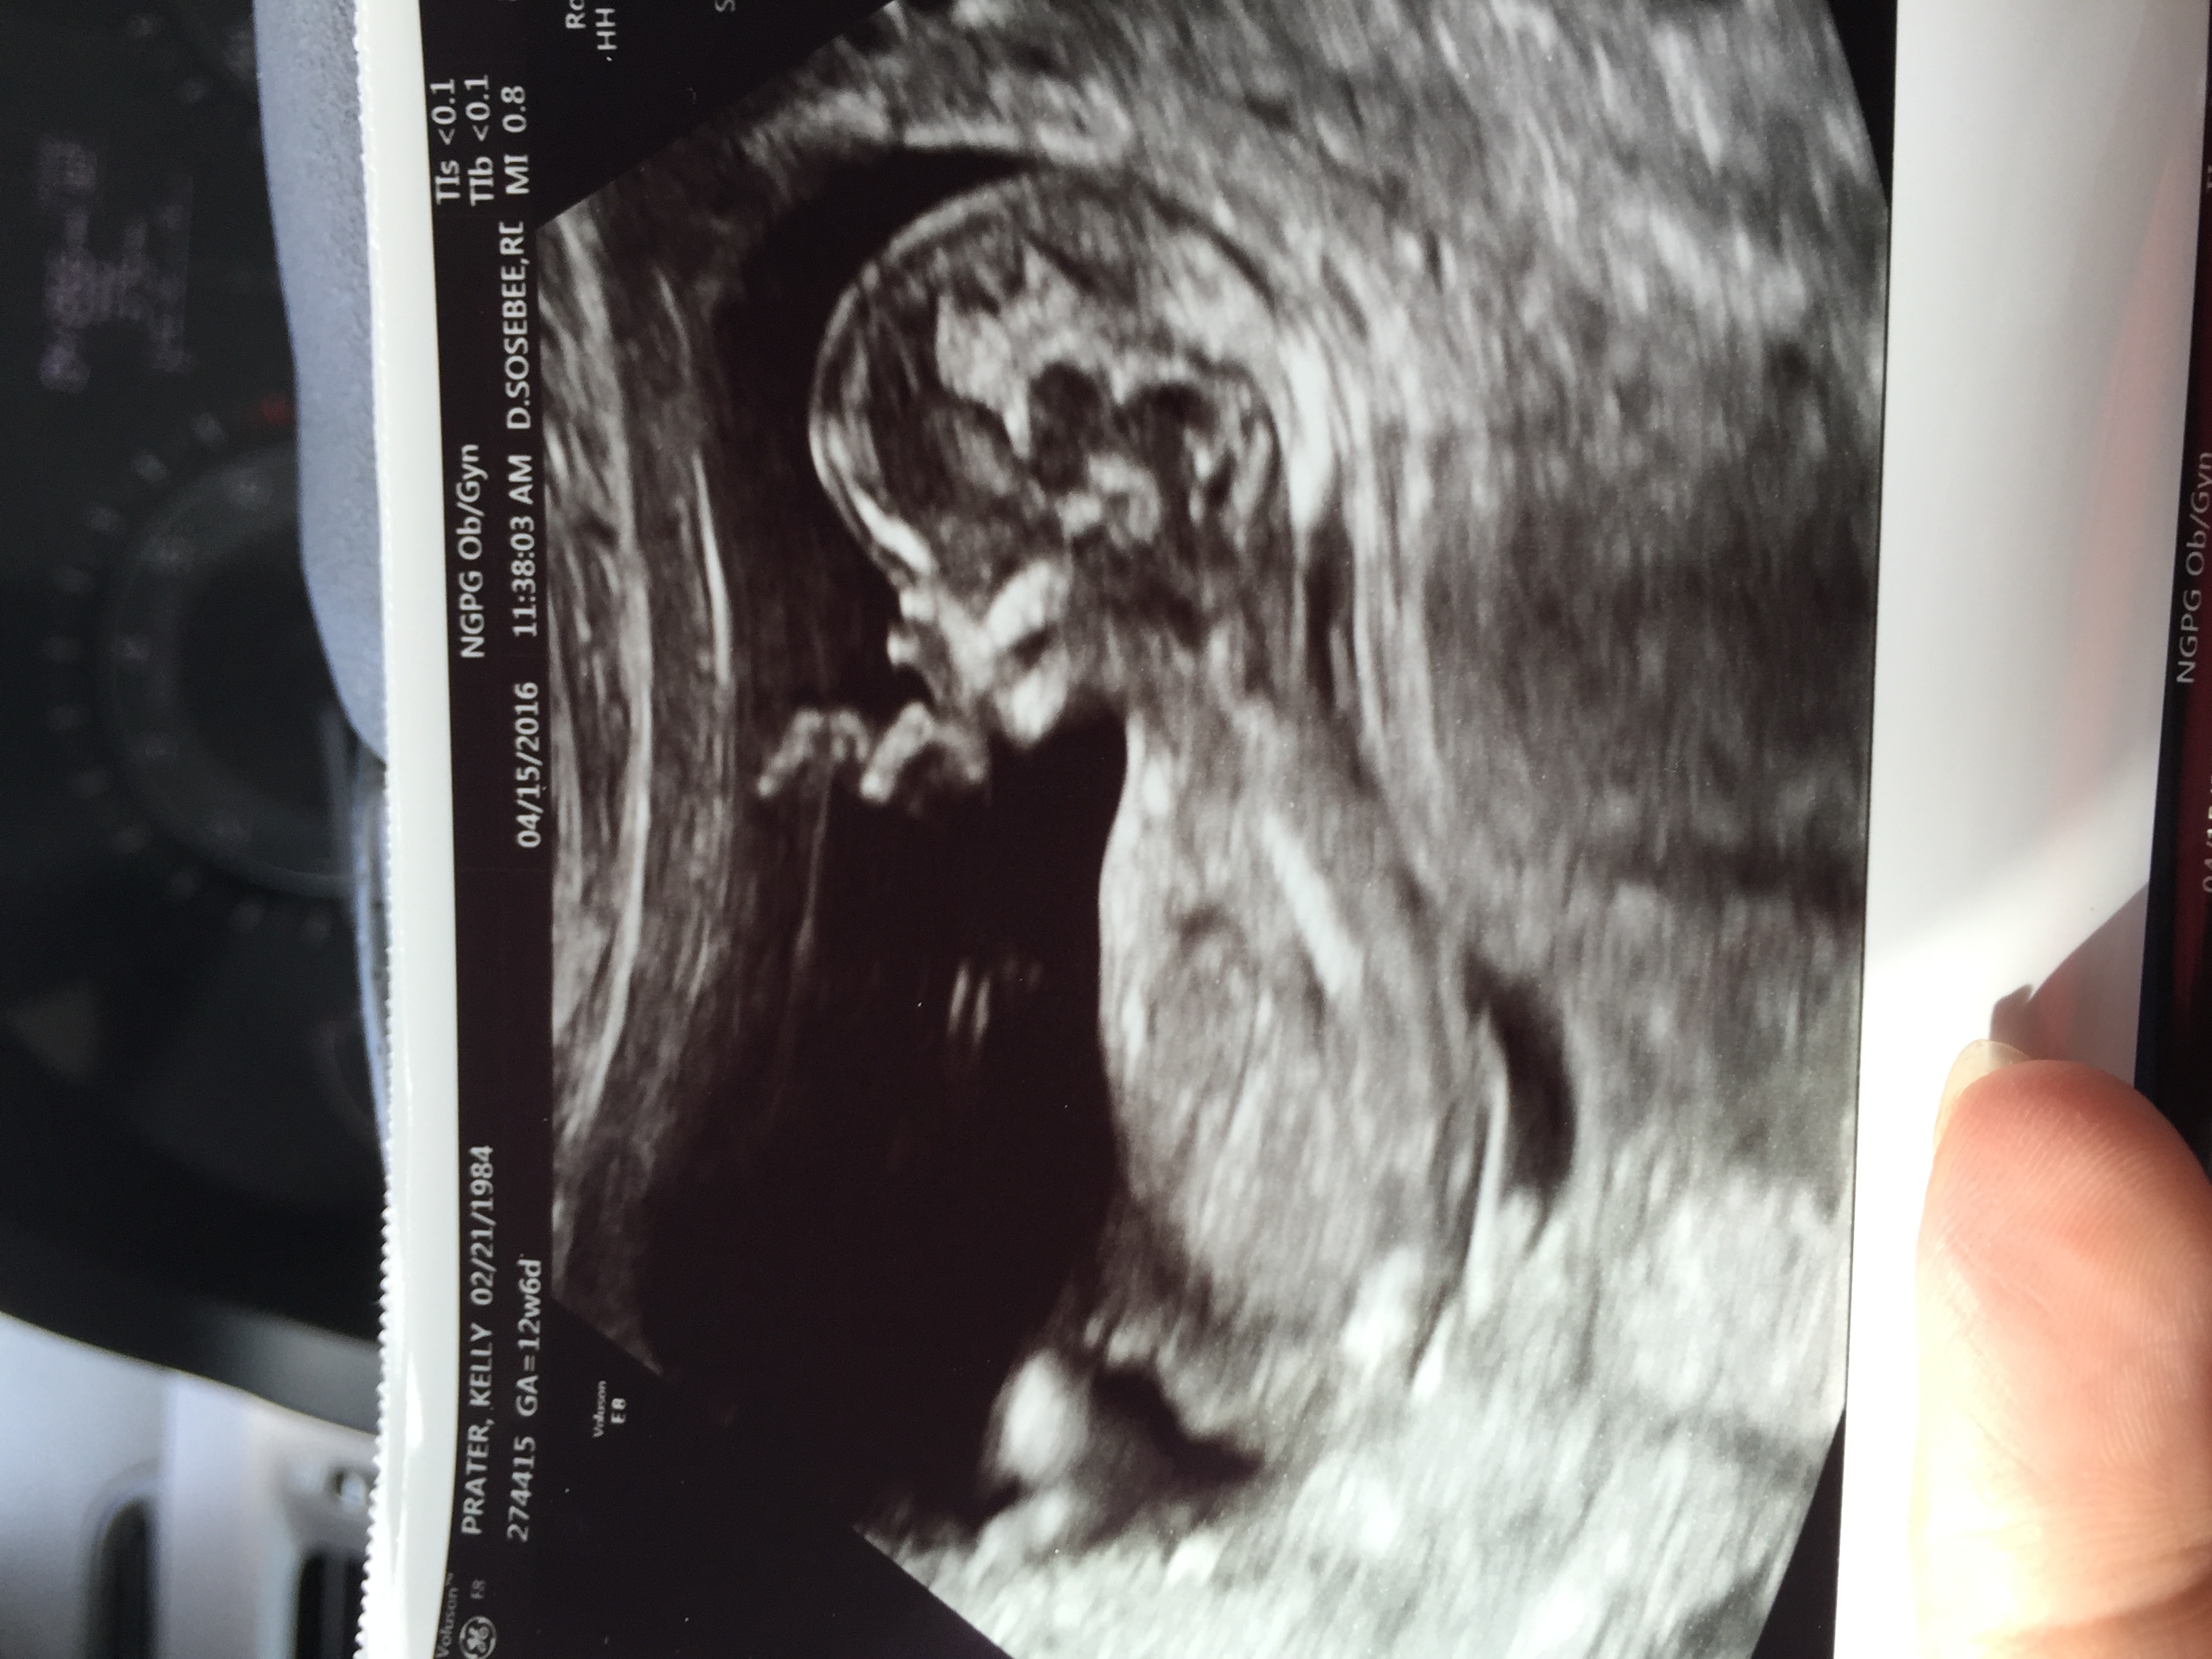

These pics were done at 12weeks 6 days. Attachment 30861Attachment 30860

Maybe a girl.

I don't think the nub is visible.

I don't see a nub

Too early